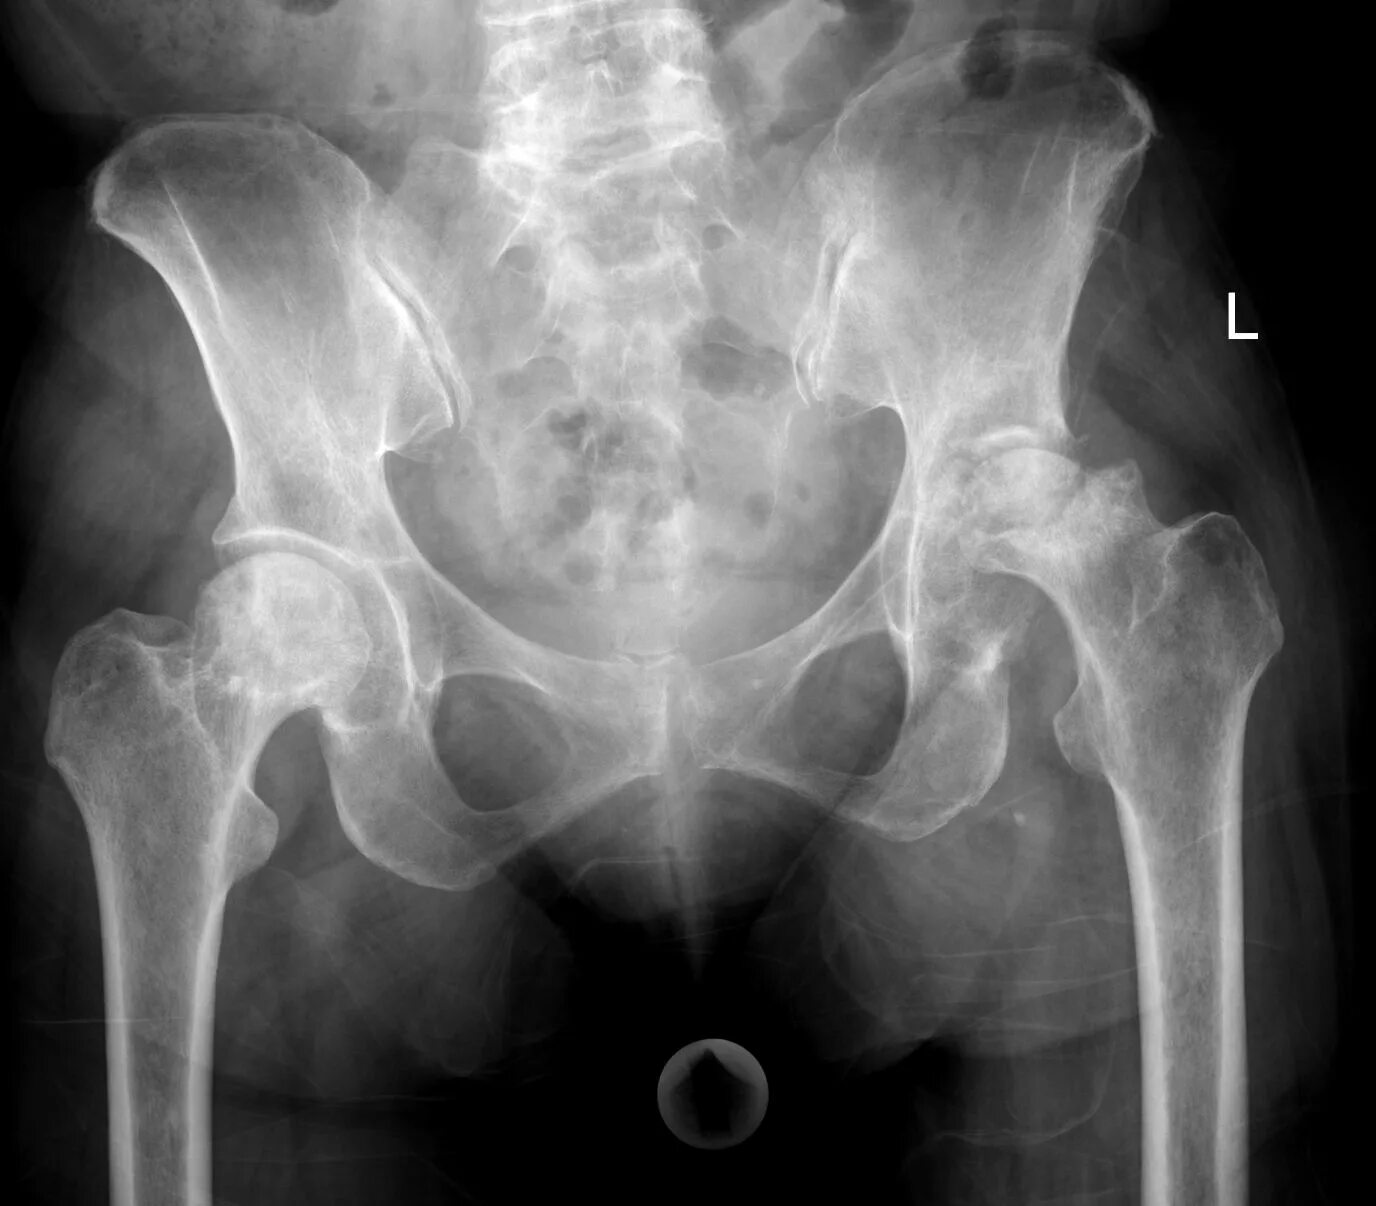

Некроз тазобедренного сустава лечение без операции